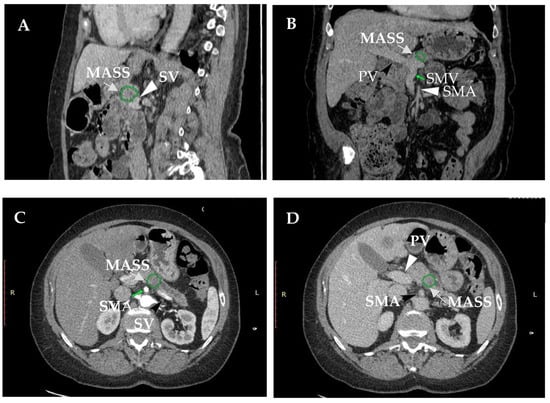

2. Definition of Resectable Pancreatic Carcinoma (R-PDAC) and Borderline Resectable (BR-PDAC)